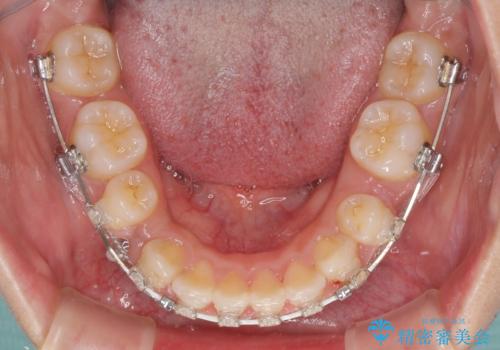

- 矯正装置

- 審美装置

- 口元の突出感と口の閉じにくさを気にして来院された患者様です。

上下左右の小臼歯4本を抜歯し、ワイヤー装置にて口元を引っ込めるよう矯正治療を行うこととしました。

上下顎ともに前突しており、特に上顎は著しい突出感でした。

また、下顎歯列には左右差があり、非対称な抜歯が必要と判断されたため、治療は困難なものとなりました。